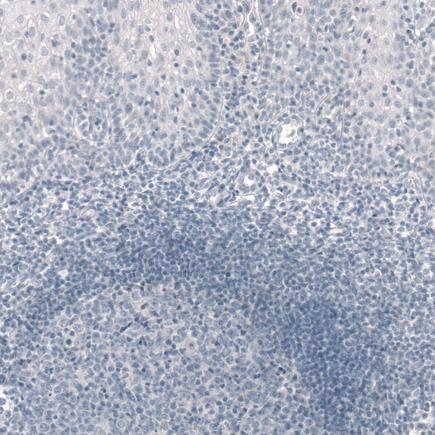

Negative control - Formalin-fixed, paraffin-embedded human tonsil tissue stained for Tpit at a 1:1000 dilution in immunohistochemical analysis.